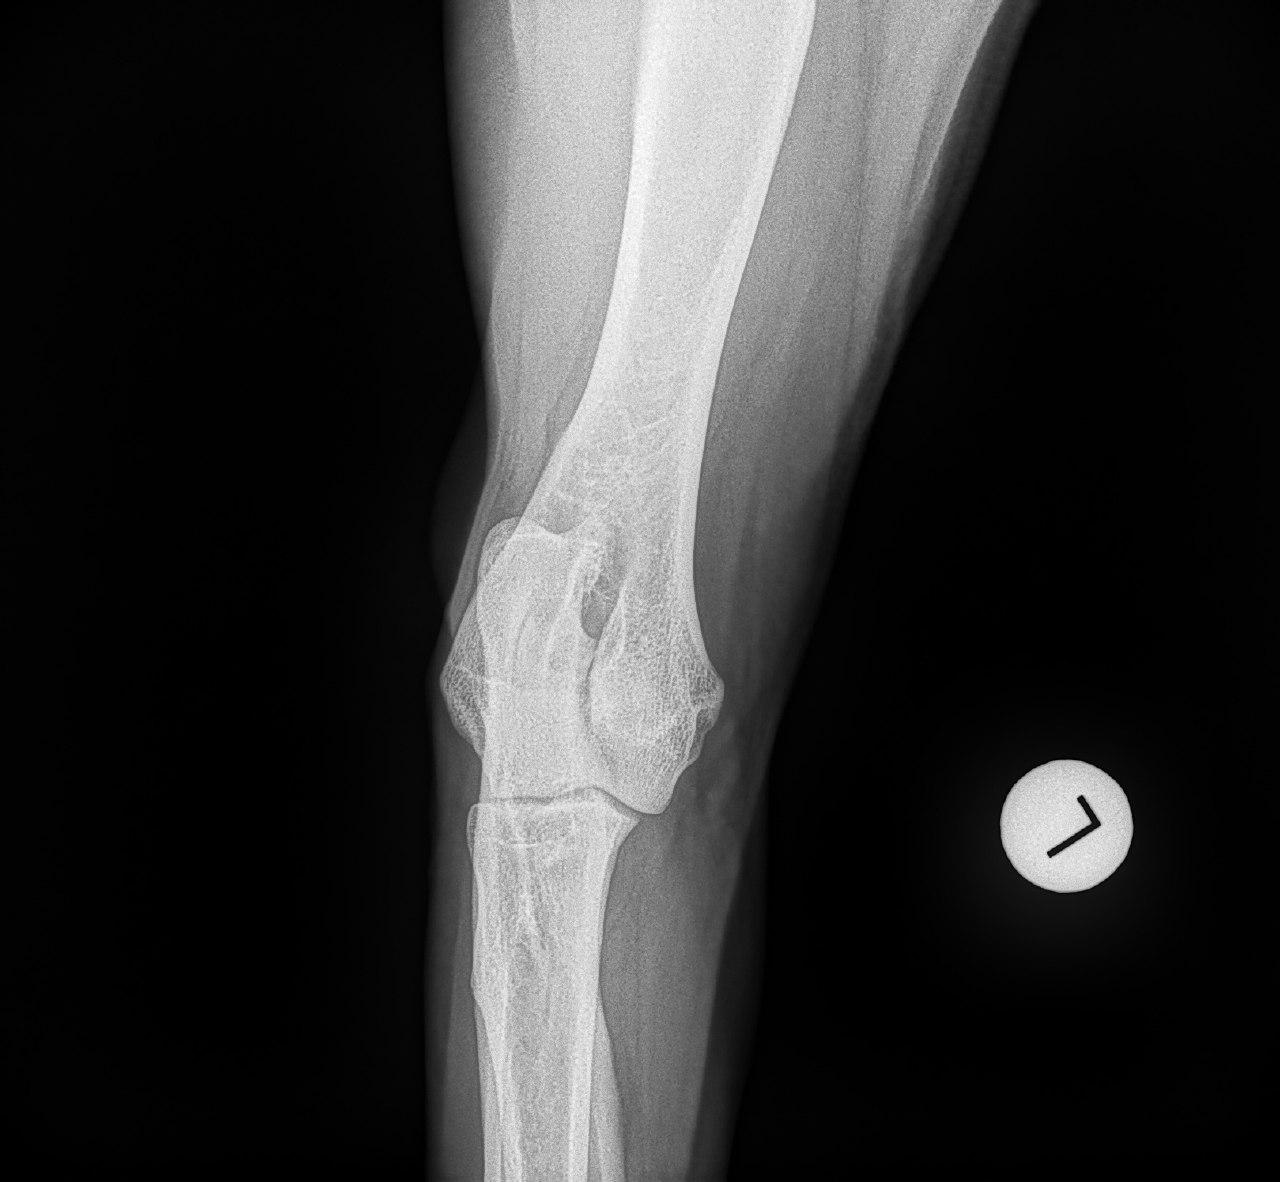

Wir haben zwar keine hd aber der Chirurg der unsere ed operiert hat hat es mir klipp und klar erklärt.

Meiner hat schwere ed rechts...im Stammbaum gibt es lediglich einmal beim Opa "ed fast normal " und trotzdem hat er sie.

Mit der HD ist das so ne Sache..... die Vererbung spielt eine sehr große Rolle, ja. Aber bei unserer Peggy Zb ist es so, dass mehrere Generationen nachweislich HD und ED frei sind und auch frei von Spondylosen. Als einziger Hund überhaupt in der gesamten Zucht hat unsere Dame alles mitgenommen, was zu kriegen war;(: sie hat nicht nur schwere HD, weil ihre Hüfte viel zu locker ist, sondern dadurch bedingt am rechten Knie bereits schwere Arthrose und hinten links eine Sehenschwäche (durch Überlastung), weshalb sie dort durchtrittig ist. Und als würde das alles nicht schon vollkommen reichen, wurden aktuell auch noch mehrere heftige Spondylosen diagnostiziert;(. An einer Stelle ist sogar schon etwas abgebrochen8|.